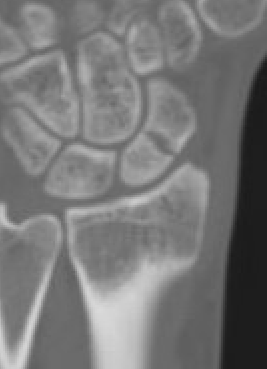

CT

Indication

- diagnose nonunion and identify size of cyst / defect

- identify humpback deformity

- helps to plan approach / size and shape of bone graft

Failure of fracture to unite at 3 months on CT scan

Nonunion with flexion / humpback deformity

Nonunion with flexion deformity